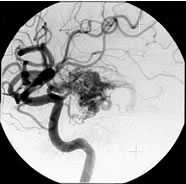

脳動静脈奇形

治療成績は病変の大きさ及び部位によって大きく異なりますが、直径3cm以内のガンマナイフ治療に適した脳動静脈奇形の場合、3年後の完全閉塞率(治癒率)は60−90%前後と報告されています。下図はガンマナイフ治療が奏功し、完全閉塞した典型的な症例です。

3年後

![]() |

| 正面像 | 側面像 |